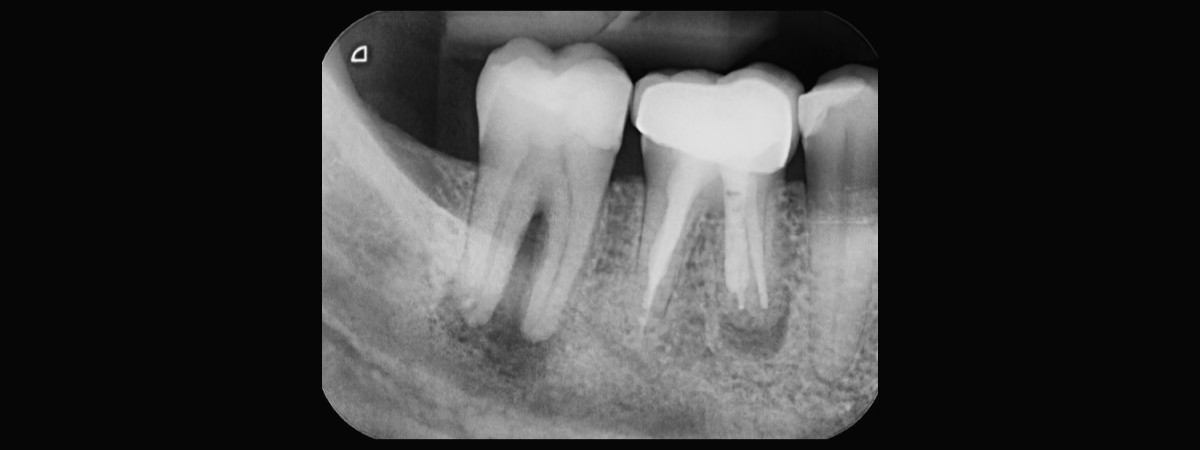

A cosa servono le radiografie RVG?

L’RVG (radiovisiografia) in odontoiatria viene utilizzata per:

- Rilevare la presenza di carie e diverse condizioni patologiche come granulomi, cisti, perdita ossea, fratture dentali o dell’osso alveolare, oltre ad altri processi patologici.

- Valutare lo stato parodontale, misurando la profondità delle tasche e l’altezza dell’osso alveolare.

- In endodonzia, l’RVG permette di confrontare le immagini dei canali radicolari, individuare canali obliterati e controllare la qualità dell’otturazione canalare.